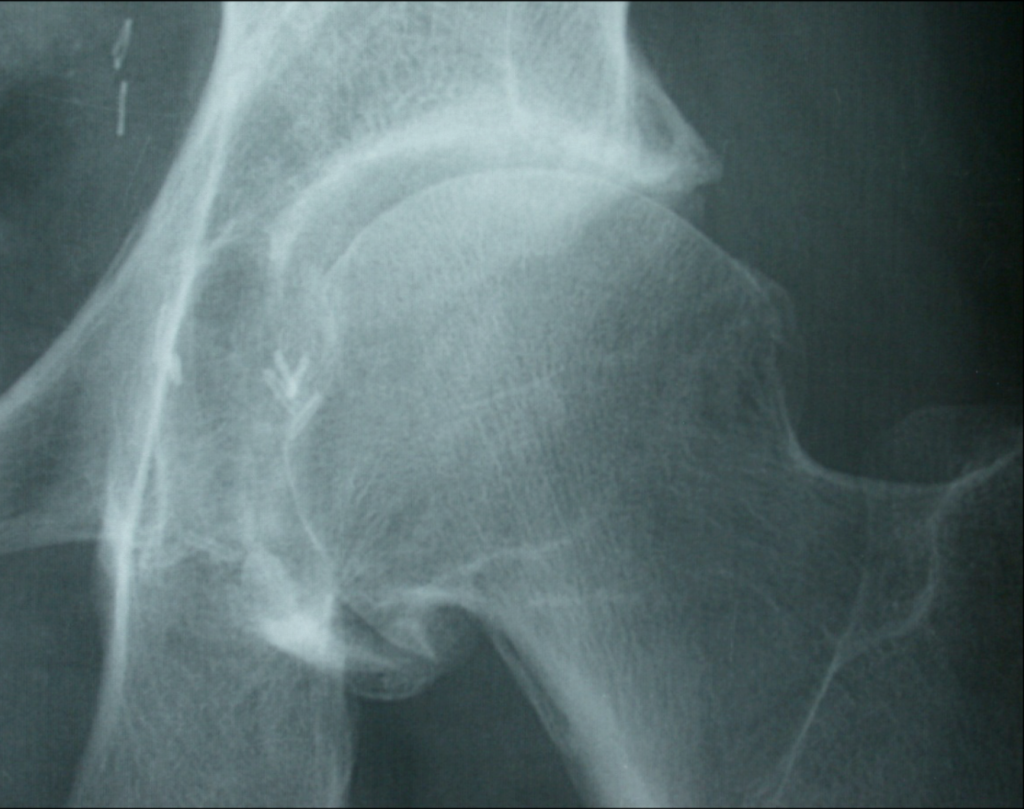

L’arthrose de la hanche, également connue sous le nom de coxarthrose, est une affection articulaire courante qui résulte de la dégradation progressive du cartilage de l’articulation de la hanche.

Cette dégénérescence du cartilage provoque une friction accrue entre les os de la hanche, entraînant des douleurs, de la raideur et une diminution de la mobilité.

Quelles sont les causes principales de la coxarthrose ?

– Les antécédents de fracture de la hanche (post traumatique)

– L’ostéonécrose aseptique de la tête fémorale

– Les maladies rhumatoïdes (polyarthrite, spondylarthropathies…)

– Les luxations congénitales de la hanche (maladies héréditaires familiales le plus souvent)

– Les séquelles de maladie de l’enfance (ostéochondrite, épiphysiolyse)

– L’hyperpression de nature statique (obésité)

– Les séquelles de conflits fémoro acétabulaires

Parfois, aucune cause n’est retrouvée, c’est ce qu’on appelle la coxarthrose primitive.

Le diagnostic de l’arthrose de la hanche est généralement confirmé par un examen clinique approfondi, des radiographies et, dans certains cas, des examens complémentaires tels que l’IRM ou l’échographie. Ces étapes permettent d’évaluer l’état de l’articulation et d’identifier les signes caractéristiques de l’arthrose.